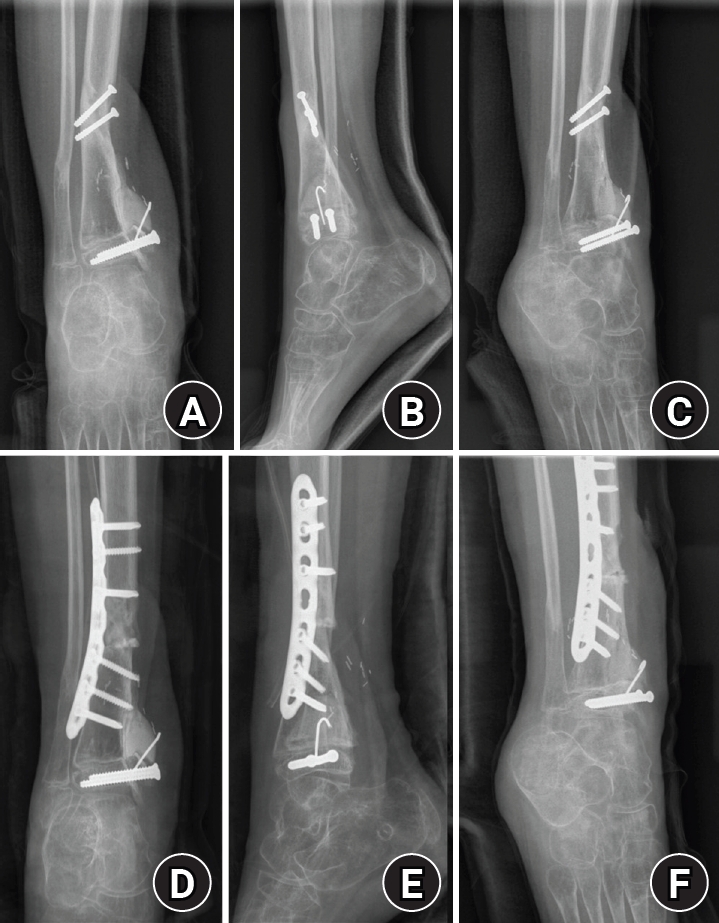

Progressive varus deformity during follow-up was treated with corrective osteotomy and plate fixation (Fig. 6).

Stage 4 (alignment and contracture management; May 29, 2017)

Corrective osteotomy for progressive varus deformity. (A) Preoperative anteroposterior radiograph obtained during follow-up, showing progressive varus deformity of the ankle. (B) Preoperative lateral radiograph obtained during follow-up. (C) Preoperative mortise radiograph obtained during follow-up. (D) Postoperative anteroposterior radiograph obtained after corrective osteotomy and plate fixation. (E) Postoperative lateral radiograph obtained after corrective osteotomy and plate fixation. (F) Postoperative mortise radiograph obtained after corrective osteotomy and plate fixation.

jmt-2026-00059f6.jpg

Fig. 6. Corrective osteotomy for progressive varus deformity. (A) Preoperative anteroposterior radiograph obtained during follow-up, showing progressive varus deformity of the ankle. (B) Preoperative lateral radiograph obtained during follow-up. (C) Preoperative mortise radiograph obtained during follow-up. (D) Postoperative anteroposterior radiograph obtained after corrective osteotomy and plate fixation. (E) Postoperative lateral radiograph obtained after corrective osteotomy and plate fixation. (F) Postoperative mortise radiograph obtained after corrective osteotomy and plate fixation.